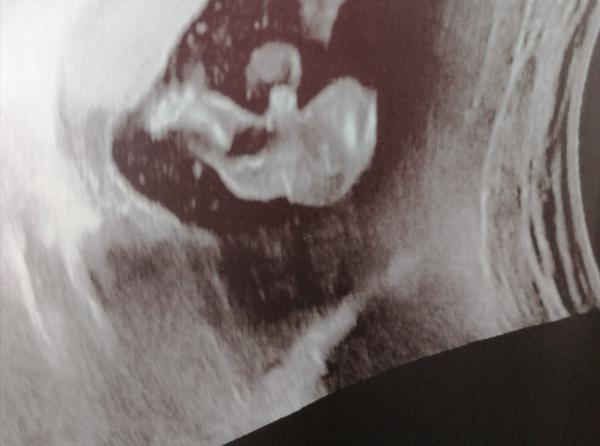

@barulilinka kluk, cekam take kluka a tohle je nas snimek

@barulilinka nemate zac. To ze to bude kluk mam potvrzene od 2 doktoru + uz u 1. Screeningu rekli na 60% kluk. Jelikoz se fotky temer nelisi, tak gratuluji 😁 mate taky kluka

@barulilinka já vás chápu, že se ujišťujete 😁 měla jsem podobnou fotku, doktor říkal, že to bude kluk, ale já si také myslela, co kdyby to byla přeci jen pupeční šňůra, doma tři holky a že by se kluk přeci jen zadařil 😁 teď při posledním ultrazvuku jsem už stopro přesvědčená, jak bylo vše krásně vidět 😄 přeji ať vám chlapeček krásně roste 💙